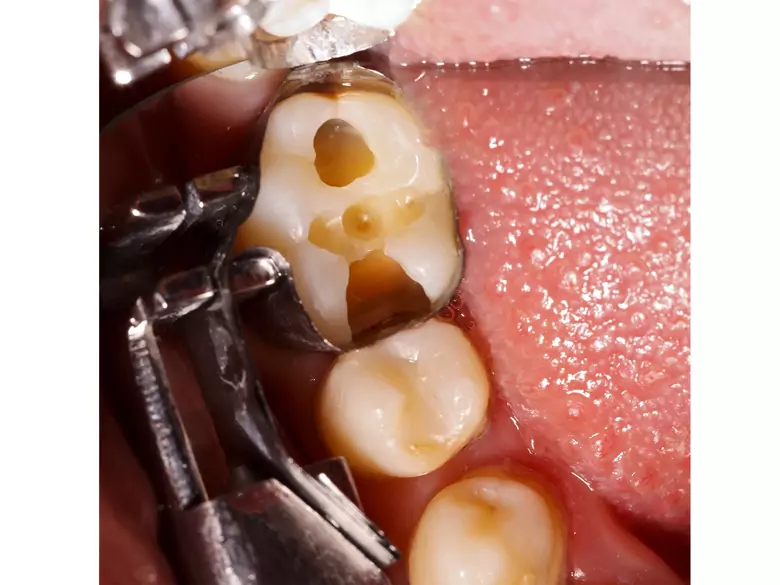

Karies, abgebrochene Zähne

EineRhadektomie ist nichts anderes als eine Situation, in der es zur Rettung eines oberen Backenzahns notwendig ist, eine der Wurzeln eines mehrwurzeligen Zahns abzuschneiden und dann zu entfernen.